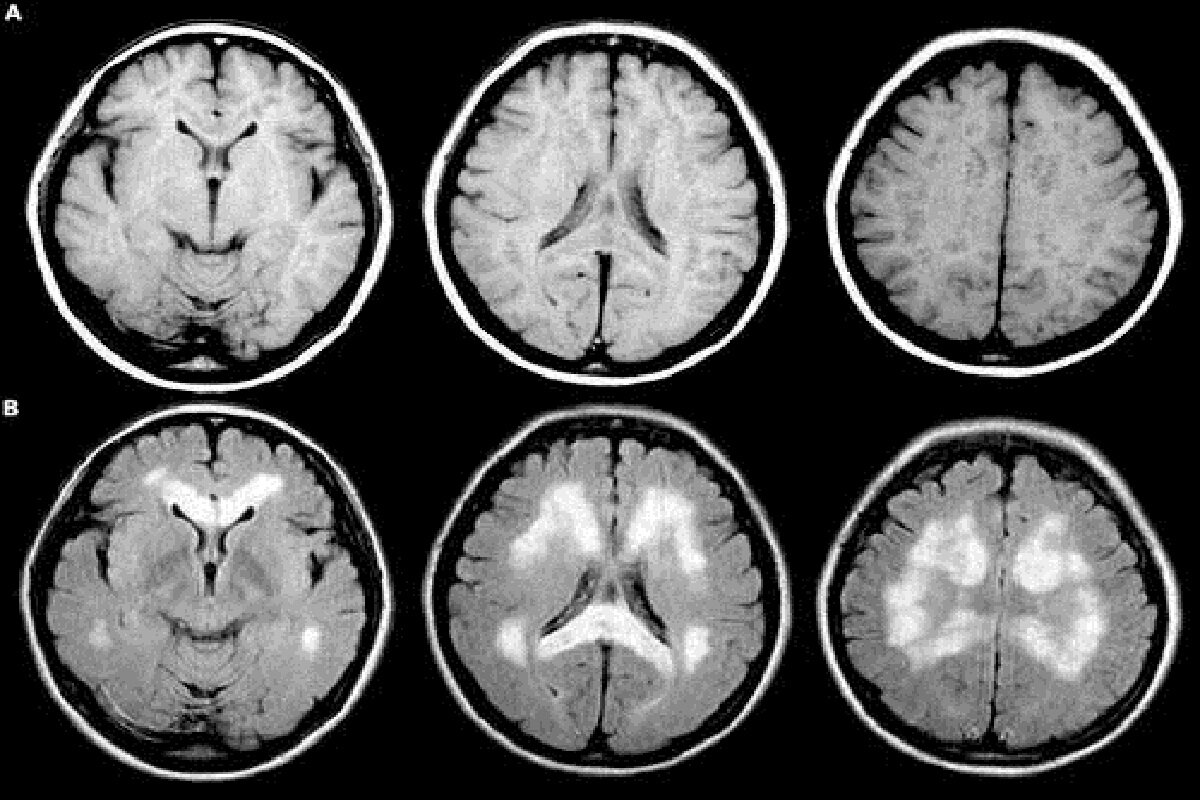

После того, как не стало актрисы Анасатсии Заворотнюк, которая на протяжении долгого времени боролась с раком мозга, врачи решили предупредить россиян о симптомах опасной болезни. Ранее стало известно, что не стало актрисы Анастасии Заворотнюк, которая на протяжении долгого времени боролась с раком мозга – глиобластомой. По данным врачей, данный вид онкологии встречается довольно редко. Например, в среднем болезнь диагностируют у 3,1 пациента на 100 тысяч человек. В возрастной категории 75−84 года глиобластома встречается чаще – у 15,03 на 100 тысяч человек. Несмотря на то, что риск столкнуться с глиобластомой ниже, чем заболеть раком груди, врачи решили предупредить россиян о симптомах болезни. Так, по словам врача-онколога, проктолога Елены Смирновой, насторожить человека должны головные боли, которые не проходят длительное время даже после приема обезболивающих препаратов. При этом врач подчеркивает, что характер боли при раке мозга отличается от болей, вызванных мигренью или стресс

По данным врачей, данный вид онкологии встречается довольно редко. Например, в среднем болезнь диагностируют у 3,1 пациента на 100 тысяч человек. В возрастной категории 75−84 года глиобластома встречается чаще – у 15,03 на 100 тысяч человек.